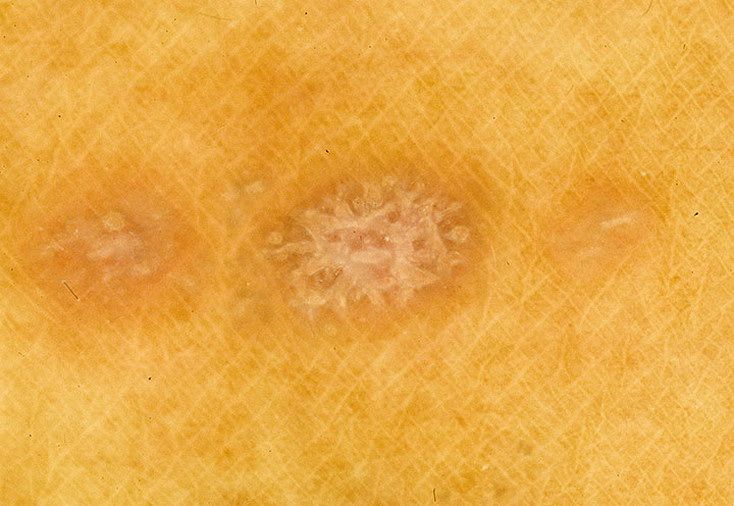

Фото Красного Плоского

Фото Красного Плоского 103 фото